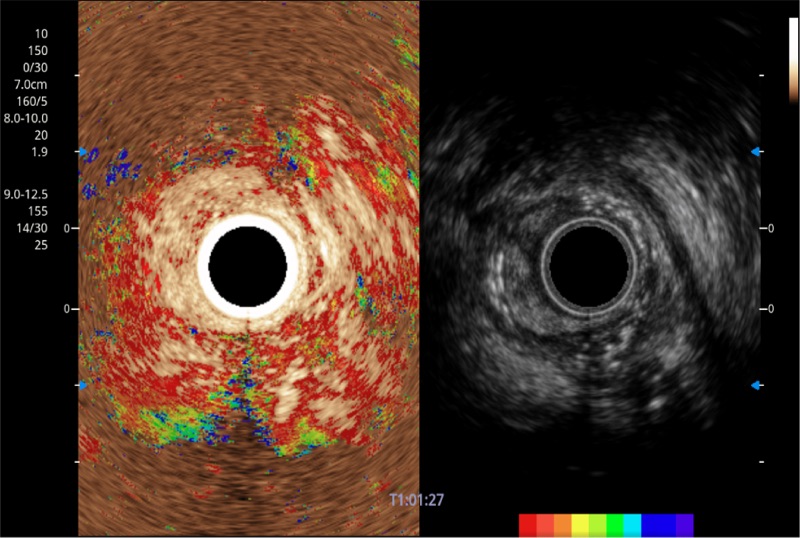

可人为将灰阶图像转变成彩色的显示方式,增强人眼对于不同回声强度的敏感度,主观上增加了图像分辨率

TIC时间强度分析曲线

具有四种造影成像效果

清晰显示胆总管及周围血管分布